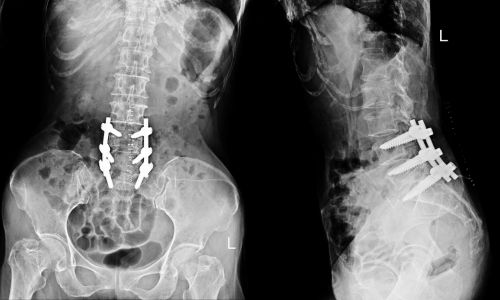

Trauma & Fracture Care

Expert management of simple and complex fractures using internal fixation (plates, screws, rods) and rehab care.

Spinal Fusion

Surgery to stabilize the spine in cases of deformity or instability.